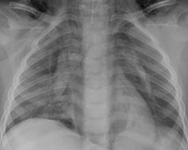

Fístula traqueoesofágica: sonda orogástrica torcida no esôfago

Do acervo de Ponthenkandath Sasidharan, MD; usado com permissão